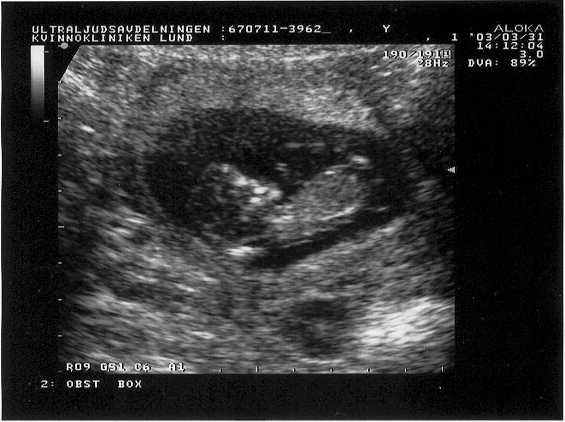

Ultra sound image from Mar. 31, 2003.